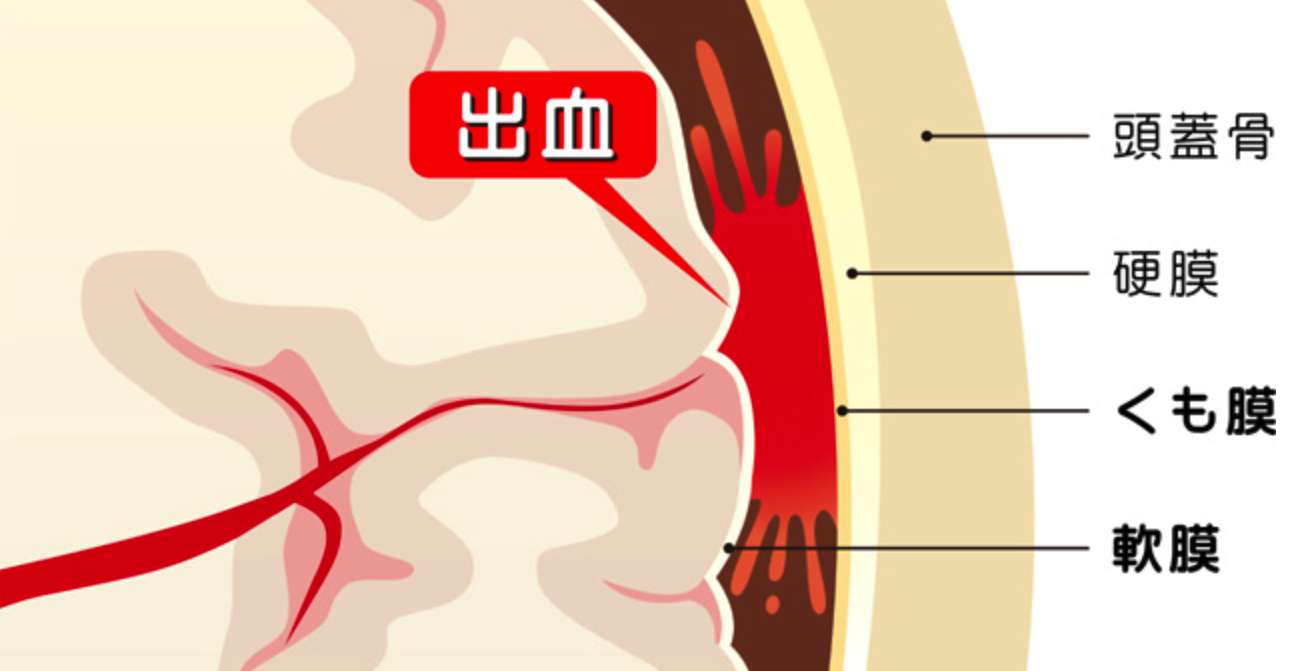

くも膜は、頭蓋骨とその内側の硬膜の下にある薄い膜です。ちなみに、くもの巣のように見えるのでそう呼ばれています。

くも膜下腔という脳の表面全体に出血が拡がり、脳圧が急激に上昇するため脳が圧迫されます。そして、突然死もあり得る危険な病気です。